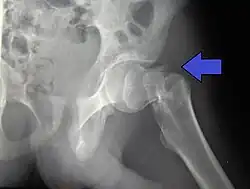

Types

.jpg)

X-rays of the affected hip usually make the diagnosis obvious; AP (anteroposterior) and lateral views should be obtained.